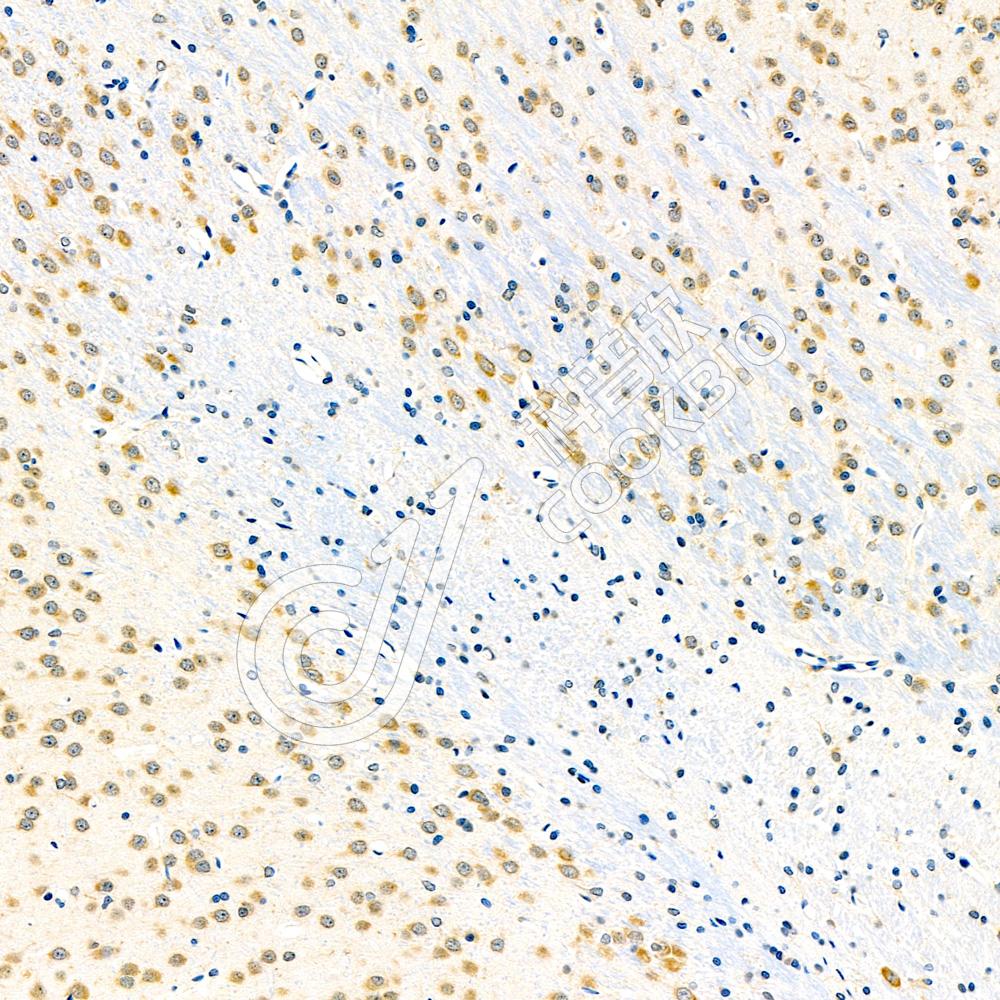

IHC检测FAK蛋白(货号 K134635).

样品: 大鼠脑, 4%多聚甲醛 (货号KSG1101) 固定12-24小时.

抗原修复: 柠檬酸抗原修复液(干粉, pH 6.0) (KSG1201), 98℃, 20分钟.

—抗: 1: 1500稀释, 4℃ 孵育过夜.

二抗: S-vision免疫组化多聚二抗(山羊抗兔),即用型 (货号KB3906), 室温孵育20分钟.